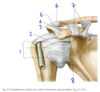

Identify #1:

What muscle attaches to #1?

1: Greater tubercle of the humerus

Supraspinatus, infraspinatus, and teres minor attach here

Which structure is labeled by #1?

Surgical neck of the humerus

Which structure is labeled by #4?

Coracoacromial ligament